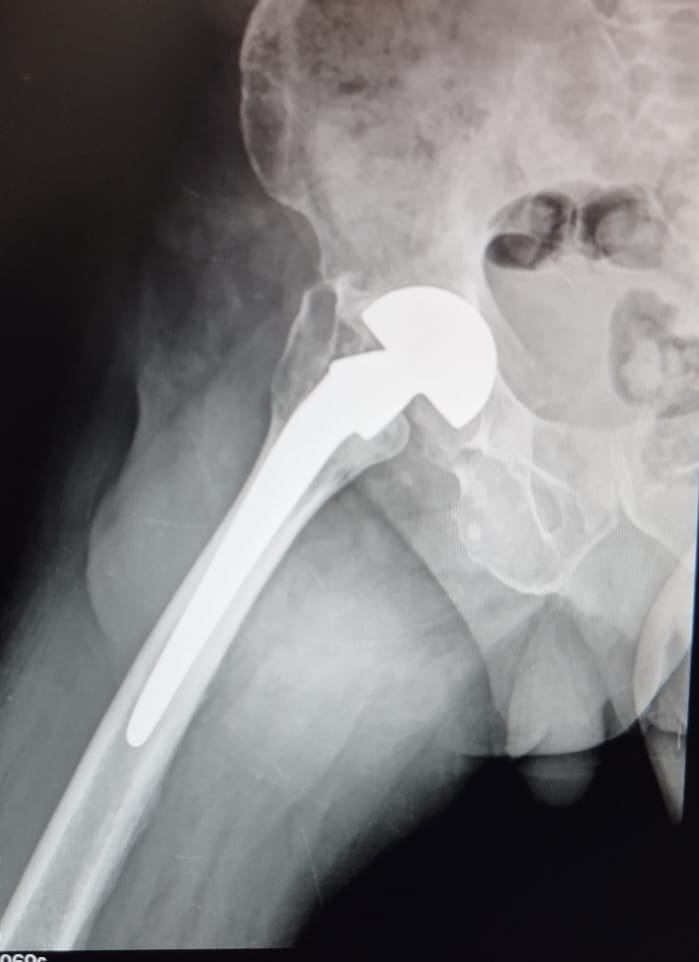

Revision hip surgery typically lasts around two hours. The surgeon removes all or part of the old implant and replaces it with a new one. In severe infection cases, surgery may be staged: first removing the implant to treat infection, then replacing it later.

The procedure may involve special implants if bones are weak or fractures are complex. Your surgeon will discuss these options and explain the expected outcome.